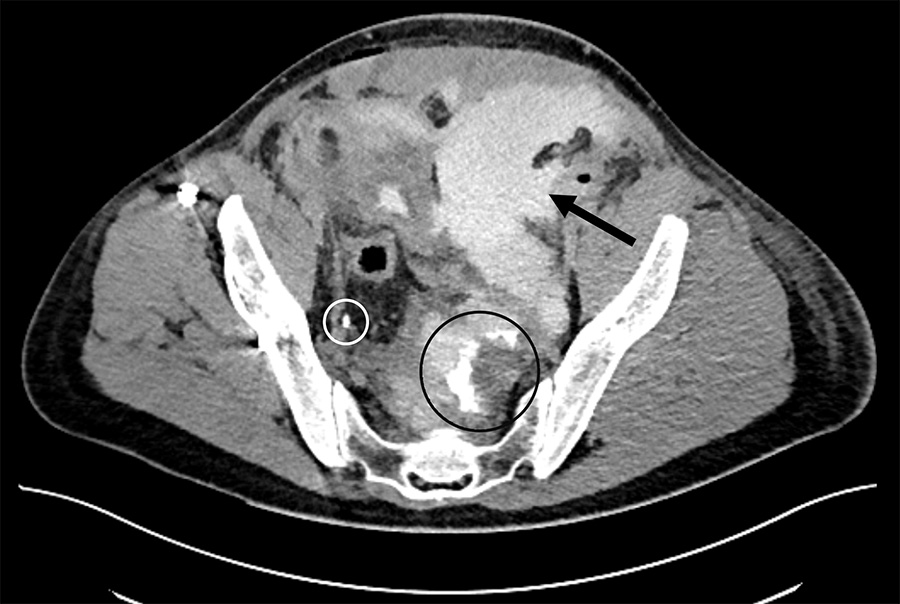

A contrast-enhanced CT with urogram was then performed, reporting a leak of contrast-enhancement liquid from the left distal ureter inside the postoperative collection. The patient was diagnosed with a compressive urinoma due to a left distal ureteral iatrogenic injury.

The uroscanner confirmed a left distal ureteral punctiform injury, detecting a filiform leakage (Fig. 2).